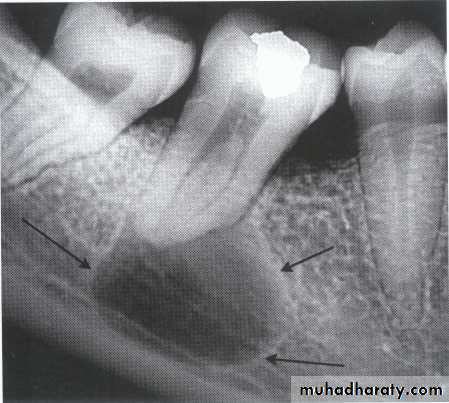

• A lesion (developmental salivary gland

• defect) below the IAC• (non- odontogenic origin).

Benign cyst: lack of peripheral cortex(retention

pseudo cyst) indicates that it originated in thesinus (non-odontogenic origin).